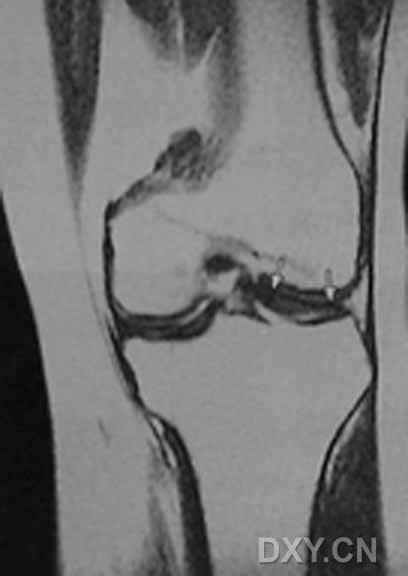

| 0级 外侧半月板表现为均匀低信号,形态规则

| I级 外侧半月板后角见灶性高信号,不与半月板关节面相接触

| Ⅱ级,见黑箭头

| III级 内侧半月板后角内见线形高信号达到半月板的关节面下缘